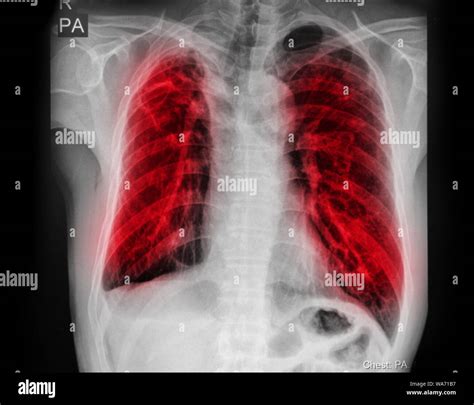

Interpreting Tb X Ray results requires expertise and experience. Radiologists look for specific signs that may indicate TB:

• Cavities: These are hollow spaces in the lungs that can form as the body tries to contain the infection.

• Nodules: Small, round opacities that can be indicative of TB infection.

• Infiltrates: Areas of increased density in the lung tissue, often seen in active TB.

• Pleural Effusion: Fluid accumulation in the pleural space, which can be a complication of TB.